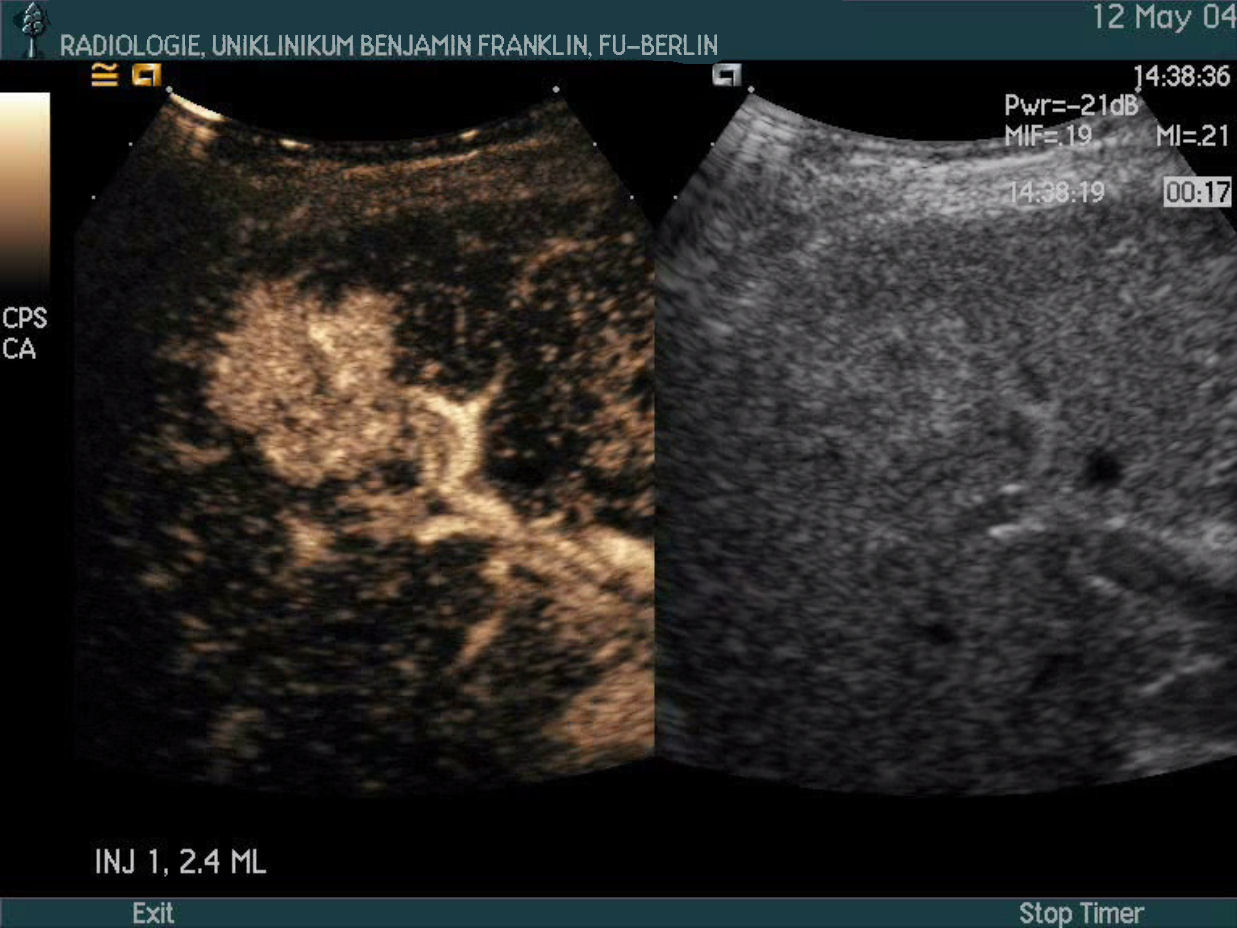

Contrast Specific Techniques

The oscillating microbubbles create a signal which is specific and different from the signal coming back from tissue. This allows separation of tissue signals and contrast agent signals based on the signal characteristics.

Using a dedicated software on the ultrasound scanner which is able to discriminate tissue- and contrast agent signals in realtime even very weak contrast agent signals can be detected and displayed on a black background (void of overlapping tissue signals).

With modern scanners, even signals from single microbubbles can be displayed and tracked.